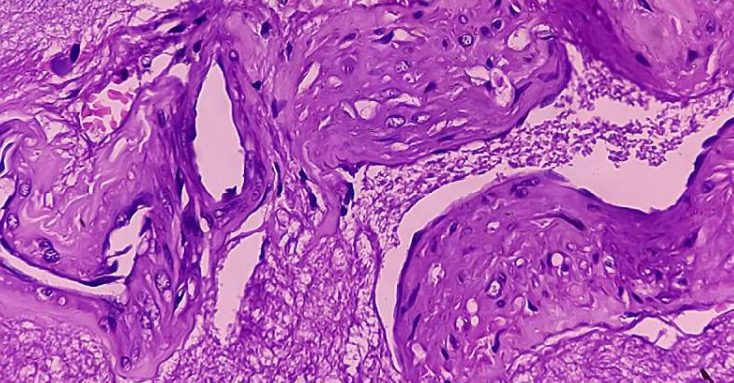

研究团队采用患者肿瘤细胞结合血管样结构,通过3D生物打印技术精确复制肿瘤微环境。共同作者袁庞博士表示:"这种方法能快速生成类器官,保留原始肿瘤特征,极大改善了肾癌研究方式。"实验显示,该模型可准确模拟肿瘤在体内的生物学行为。

传统实验室模型存在一致性差、无法反映真实肿瘤特征等问题。新型肾癌类器官技术克服了这些限制,实现了多种疗法的快速测试。研究人员指出,这为临床治疗前的方案筛选提供了可靠工具。